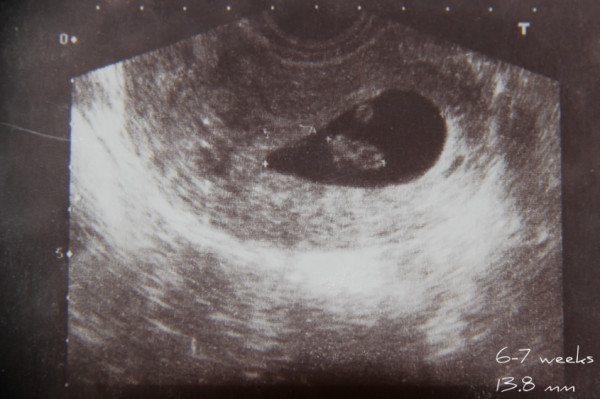

Фотографии на ранних этапах беременности